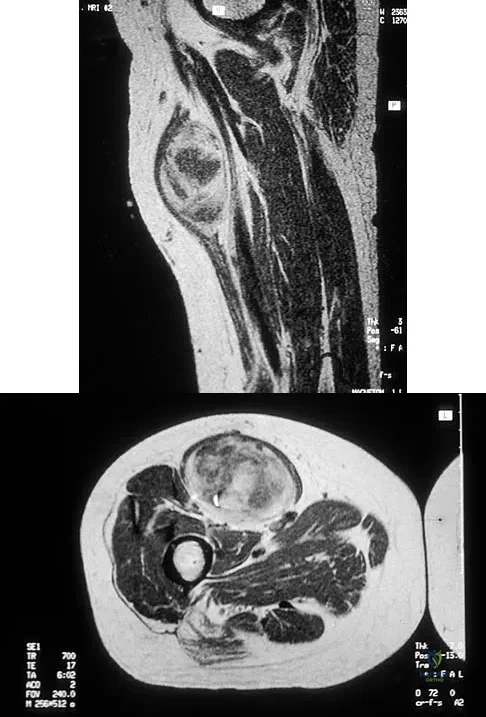

Figures 30a and 30b show the MRI scans of a 51-year-old woman who has had an enlarging soft-tissue mass in her right thigh for the past 18 months. Examination reveals no inguinal adenopathy. Results of a biopsy show a high-grade sarcoma. A bone scan is unremarkable, and a CT scan of the chest shows no evidence of pulmonary metastasis. According to the Musculoskeletal Tumor Society (MSTS) staging system, the tumor should be classified as what stage?

Explanation